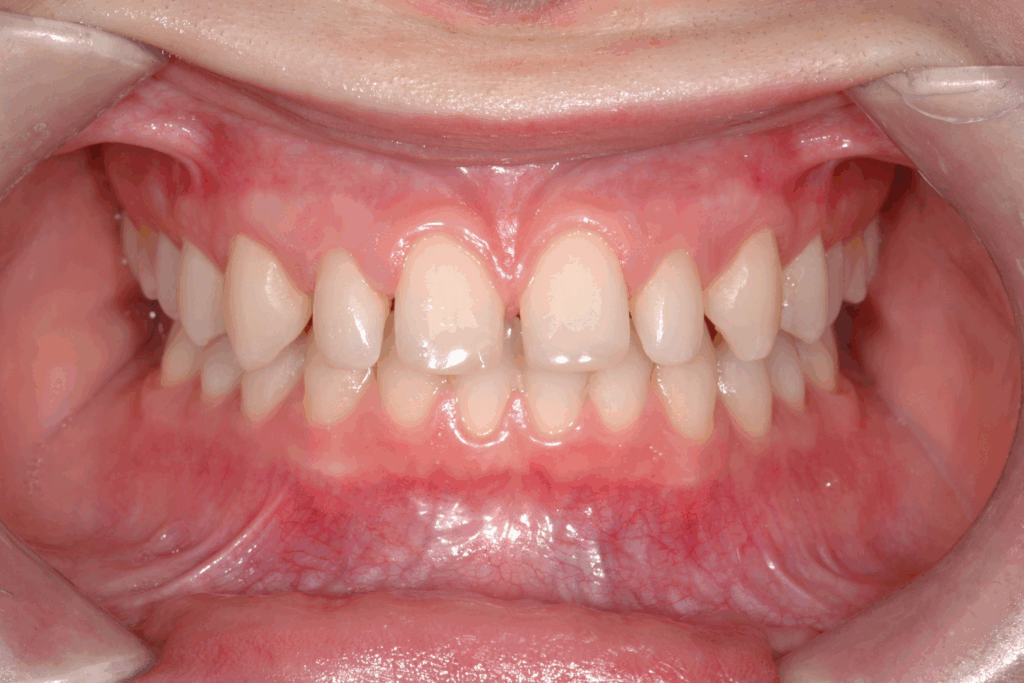

La prima fase del trattamento è stata un’analisi approfondita. Durante il check-up, abbiamo confermato la diagnosi di agenesia dei secondi molari permanenti inferiori, una condizione congenita che lascia spazi vuoti nell’arcata. Abbiamo inoltre rilevato che gli incisivi superiori erano di dimensioni ridotte rispetto al resto dei denti e che la paziente presentava un morso profondo, con gli incisivi superiori che coprivano eccessivamente quelli inferiori. Questa valutazione completa ci ha permesso di creare un piano di trattamento personalizzato e preciso, tenendo conto di tutte le problematiche presenti.